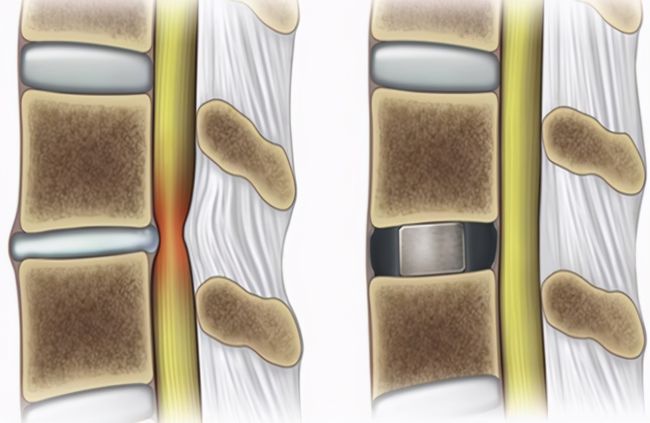

OLIF手术

椎间隙撑开后达到间接减压的目的

OLIF微创手术是目前流行的一种微创椎间融合手术,通过撑开椎间隙达到间接减压的目的。手术从腰部斜前侧方入路,从自然间隙到达腰椎,椎间处理后椎间隙撑开,做一个滑脱的复位,然后再根据患者情况I期或II期后路置入钉棒固定。